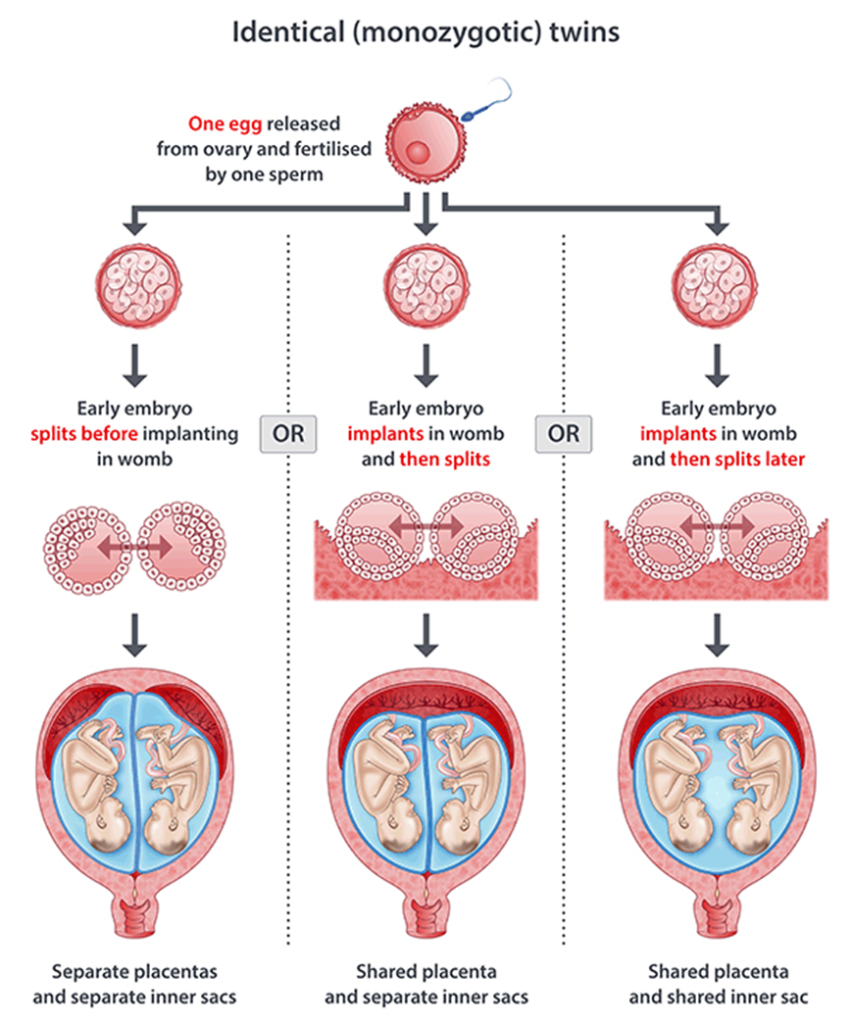

ஒருகருவுற்றமுட்டைமற்றொன்றில்பிளவுபடுகிறது, இதன்விளைவாகஒரேமாதிரியானபலகருக்கள்உருவாகின்றன.இந்தவகையானகர்ப்பத்தின்விளைவாகஒரேமாதிரியானஇரட்டையர்கள் (அல்லதுஅதற்குமேற்பட்டவர்கள்).ஒரேமாதிரியானஇரட்டையர்கள்சகோதரஇரட்டையர்களைவிடகுறைவாகவேகாணப்படுகின்றன.

- ஒரே மாதிரியான குழந்தைகள் மோனோ சைகோடிக் (Monozygotic) என்று அழைக்கப்படுகின்றன. மோனோ சைகோடிக் உடன் பிறப்புகள் ஒருமுட்டையிலிருந்து வருகிறார்கள். இந்தவழக்கில், முட்டை ஒரு விந்தணுவால் கருவுற்றது, பின்னர் இரண்டு அல்லது அதற்குமேற்பட்ட கருக்களாகப்பிரிக்கப்படுகிறது. இந்தக்குழந்தைகள் அனைத்தும் ஒரேபாலினமாக இருக்கும். அவை அனைத்தும் ஒரேமாதிரியான மரபணுக்களைக்கொண்டிருக்கும்.

உயிரணுக்களின் ஆரம்பநிலையில் கருப்பையில் பதியும்போது, கருப்பையின் புறணி நஞ்சுக்கொடி எனப்படும் மற்றொருவகை திசுக்களை வளர்க்கத்தொடங்குகிறது. வளரும்கரு தொப்புள்கொடி எனப்படும் குழாய் மூலம் நஞ்சுக்கொடியுடன் இணைக்கப்பட்டுள்ளது. நஞ்சுக்கொடி வளர்ந்துவரும் கருவுக்கு அனைத்து ஊட்டச்சத்துக்களையும் இரத்தத்தையும் வழங்குகிறது. அம்னோடிக்சாக் (amniotic sac) எனப்படும் திரவப்பைக்குள் கருவளர்கிறது. அம்னோடிக்சாக்கின் உள்புறணி அம்னியன் என்று அழைக்கப்படுகிறது. வெளிப்புறபுறணி chorion என்று அழைக்கப்படுகிறது, மற்றும் நஞ்சுக்கொடியுடன் இணைக்கிறது.எடுத்துக்காட்டாக:

- இரட்டையர்கள் டைகோரியானிக் டயம்னியோடிக் ஆக இருக்கலாம். இரட்டையர்களுக்கு தனித்தனி அம்னியன்கள் மற்றும் கோரியான்கள் உள்ளன. இதுகுறைந்த ஆபத்துள்ள இரட்டைகர்ப்பத்தின் வகை.

- இரட்டையர்கள் மோனோ கோரியோனிக்டயம்னியோடிக் ஆக இருக்கலாம். இரட்டையர்கள் ஒரேகோரியன் மற்றும் நஞ்சுக்கொடியைப்பகிர்ந்து கொள்கிறார்கள். அவைதனித்தனி அம்னோடிக்பைகளில் வளரும்.

- இரட்டையர்கள் மோனோ கோரியோனிக் மோனோ அம்னியோடிக் ஆக இருக்கலாம். இரட்டையர்கள் ஒரே அம்னியன், கோரியன் மற்றும் நஞ்சுக்கொடியைப்பகிர்ந்து கொள்கிறார்கள்.

- சியாமி இரட்டையர்கள் (இணைந்தஇரட்டையர்கள்). கருக்கள் உடல்ரீதியாக ஒன்றாக இணைக்கப்பட்டுள்ளன. இதுமிகவும் அரிது.